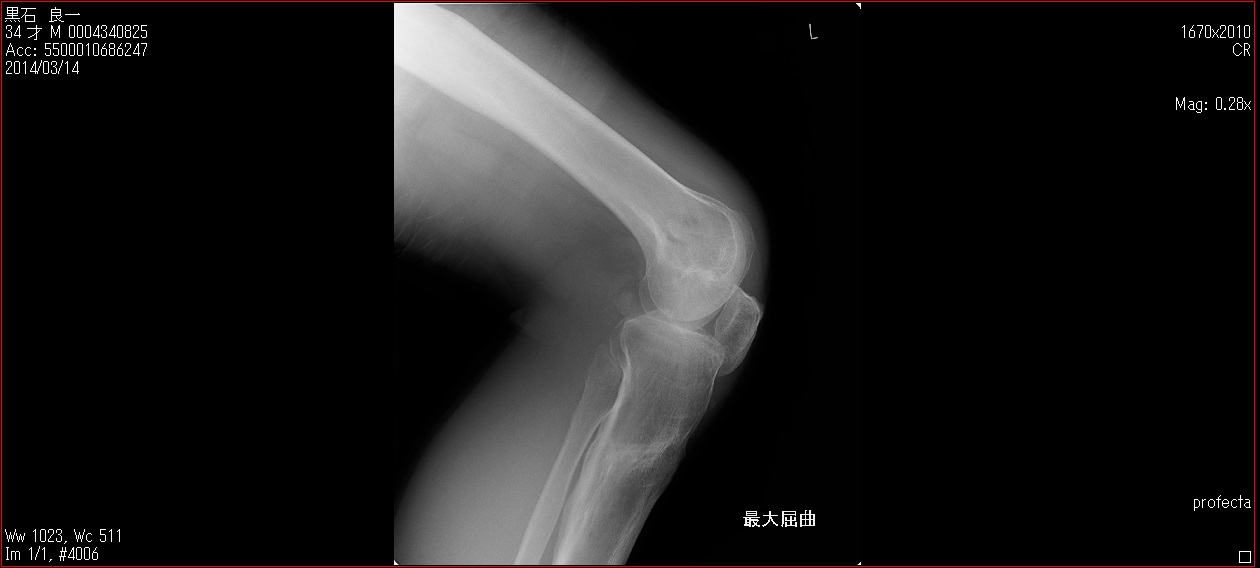

[Ortho] patella baja

Пациент 27 лет приехал для удлинения роста по эстетическим показаниям. Метод: крослатеральное двухэтапное удлинение голеней 4см и бедер 3 см.  Между этапами удлинения уезжал к себе домой в Японию на реабилитацию. Между этапами удлинения движения в коленных суставах разгибание полное сгибание 90-85. После выписки (февраль 2012) даны соответствующие указание постепенно возрастающей нагрузки и ЛФК коленных суставов.

В настоящий момент жалобы на ограничение сгибания в коленных суставах. Снимки прилагаются.

Вопрос: почему возникло такое осложнение? Поверьте приходилось удлинять намного больше, а тут всего на 3-4 см и такое осложнение на обеих конечностях у одного пациента?

Что можно сделать? У кого есть опыт лечения patella baja?